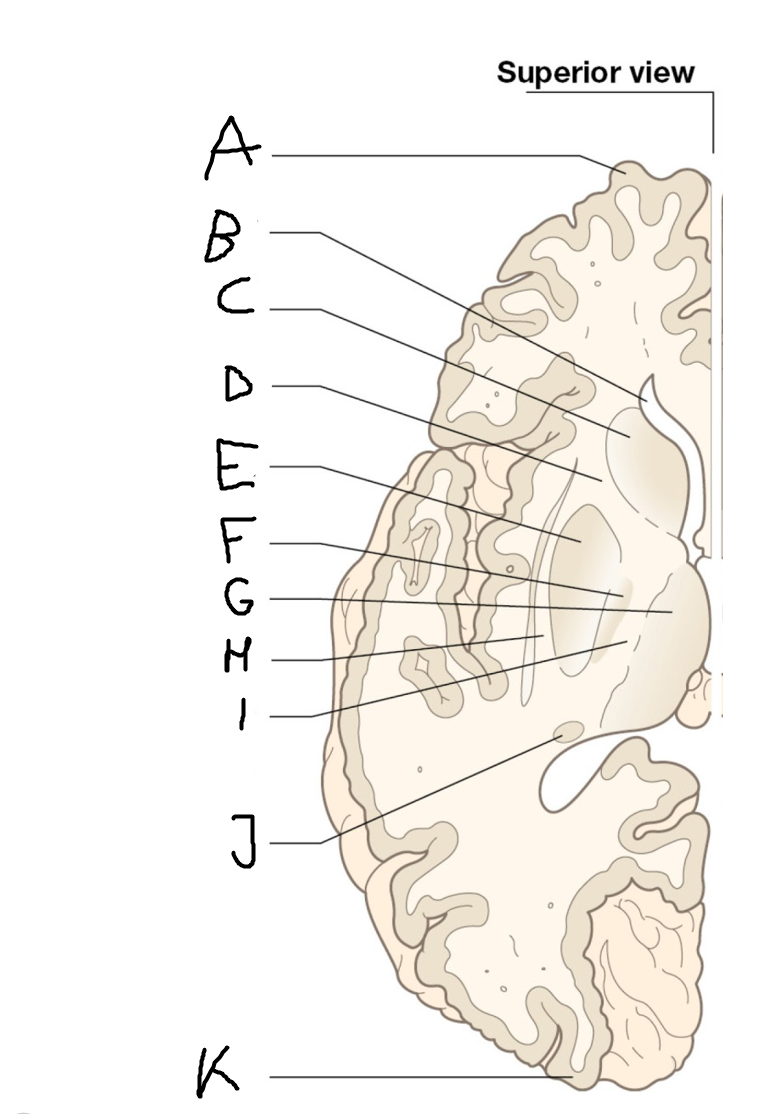

internal capsule (posterior limb)

B

anterior horn of lateral ventricle

C

head of caudate nucleus

D

internal capsule (anterior limb)

E

putamen

F

globus pallidus

G

Thalamus

H

External capsule

I

internal capsule (posterior limb)

J

tail of caudate nucleus